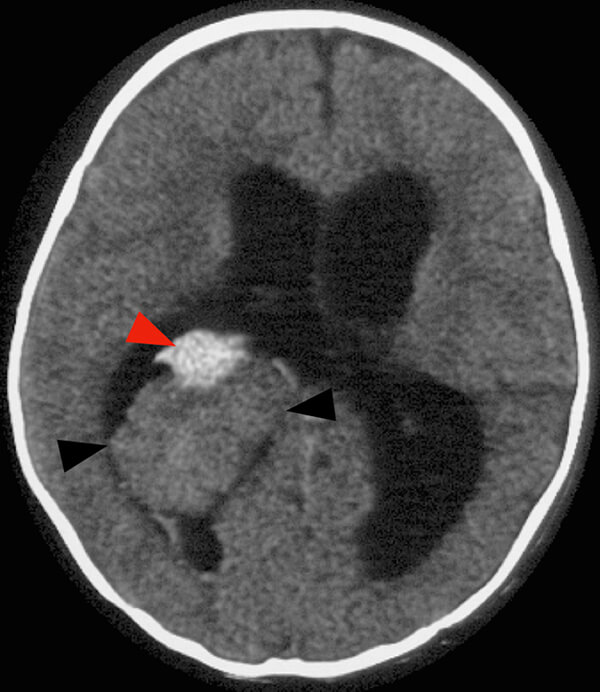

- Συνήθως θηλώματα, σπανιότερα καρκινώματα. Επίσης στη διαφορική διάγνωση υπεισέρχονται τα έκτοπα ενδοκοιλιακά μηνιγγιώματα. Έχουν πλούσια αιματώση από τις χοριοειδείς αρτηρίες και συχνά παρουσιάζονται με αιμορραγία και υδροκέφαλο.

Αιμαγγειοβλαστώματα

- Μπορεί να είναι πολλαπλά, ακόμη και εκτός της πλήρους έκφράσεως του συνδρόμου von Hippel Lindau. Εντοπίζονται στον οπίσθιο κρανιακό βόθρο ή τον νωτιαίο μυελό. Αν και είναι σαφώς αφοριζόμενοι όγκοι, στερούνται κάψας. Συχνά αντλούν αιμάτωση από την επαφή τους με το παρακείμενο εγκεφαλικό παρέγχυμα. Σε μερική αφαίρεση, υποτροπιάζουν συχνά. Δεν προκαλούν απομακρυσμένες μεταστάσεις.

- Τυπικά παρουσιάζονται λόγω χωροκατακτητικών σημείων με αύξηση της ενδοκρανίου πιέσεως και υδροκεφαλία από απόφραξη της 4ης κοιλίας. Σε μυελική εντόπιση, το εντοπισμένο άλγος με προϊούσα κινητικο-αισθητική διαταραχή, οδηγεί χωρίς θεραπεία σε παραπληγία ή τετραπληγία. Η αιμορραγία είναι σπάνια.